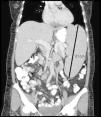

Tras permanecer 7 años asintomática, consulta a nuestro servicio por dolor y distensión abdominal. Se constata esplenomegalia masiva (fig. 1) y bicitopenia persistente (hematocrito 24%; leucocitos: 1.000/mm3, neutrófilos 670/mm3). Analítica: velocidad de sedimentación globular 97mm en primera hora, FR de 47 UI/ml (LSN: 14 UI/ml) y anticuerpo antivimentina citrulinada mutada (anti-VCM)≥300 U/ml, con ANA, anti-DNAn, anti-Smith, anti-RNP, anti-Ro, anti-La, anticuerpos anticardiolipinas y crioglobulinas negativas, y normocomplementemia. Serologías virales para virus de la inmunodeficiencia humana y virus de hepatitis B y C, negativas. Ecografía de ambas manos sin signos de sinovitis. Radiografías con escasas erosiones. Biopsia de médula ósea reactiva, con hiperplasia de la serie granulocítica, sin células neoplásicas, y citometría de flujo sin signos de malignidad. Debido a la magnitud de la esplenomegalia y a la ausencia de actividad articular en los últimos años, se considera entre otros diagnósticos diferenciales al linfoma esplénico, por lo que se realiza esplenectomía. El examen anatomopatológico evidencia un proceso inflamatorio crónico inespecífico. Se arriba al diagnóstico de síndrome de Felty. Tras la esplenectomía se realiza tratamiento con glucocorticoides. Inicia con 60mg/d de prednisona, reduciendo lentamente la dosis gradualmente en 2 años. Logra mejoría del cuadro hematológico (hematocrito 42%; leucocitos: 3.500/mm3, neutrófilos 40%) y normalización de los reactantes de fase aguda.

A las 2 semanas de haber suspendido los corticoides, presenta dolor torácico, taquipnea y disnea, constatándose derrame pericárdico masivo (fig. 2) y requerimiento de pericardiocentesis (1.400 cc de líquido serohemático). Cultivo de líquido pericárdico: negativo para gérmenes comunes y bacilos ácido-alcohol resistentes. Anatomía patológica: pericarditis crónica esclerosa inespecífica. La tomografía computarizada de tórax, abdomen y pelvis no mostraron imágenes patológicas compatibles con tuberculosis ni con neoplasias. Realiza tratamiento con colchicina y prednisona 40mg/día, y posteriormente azatioprina 150mg/día, con resolución completa del derrame pericárdico. Se redujo lentamente la dosis de prednisona durante 2 años. Destacamos que la paciente no presentó signos clínicos ni ecográficos de artritis activa durante los procesos sistémicos relatados, ni destrucción articular radiográfica importante.